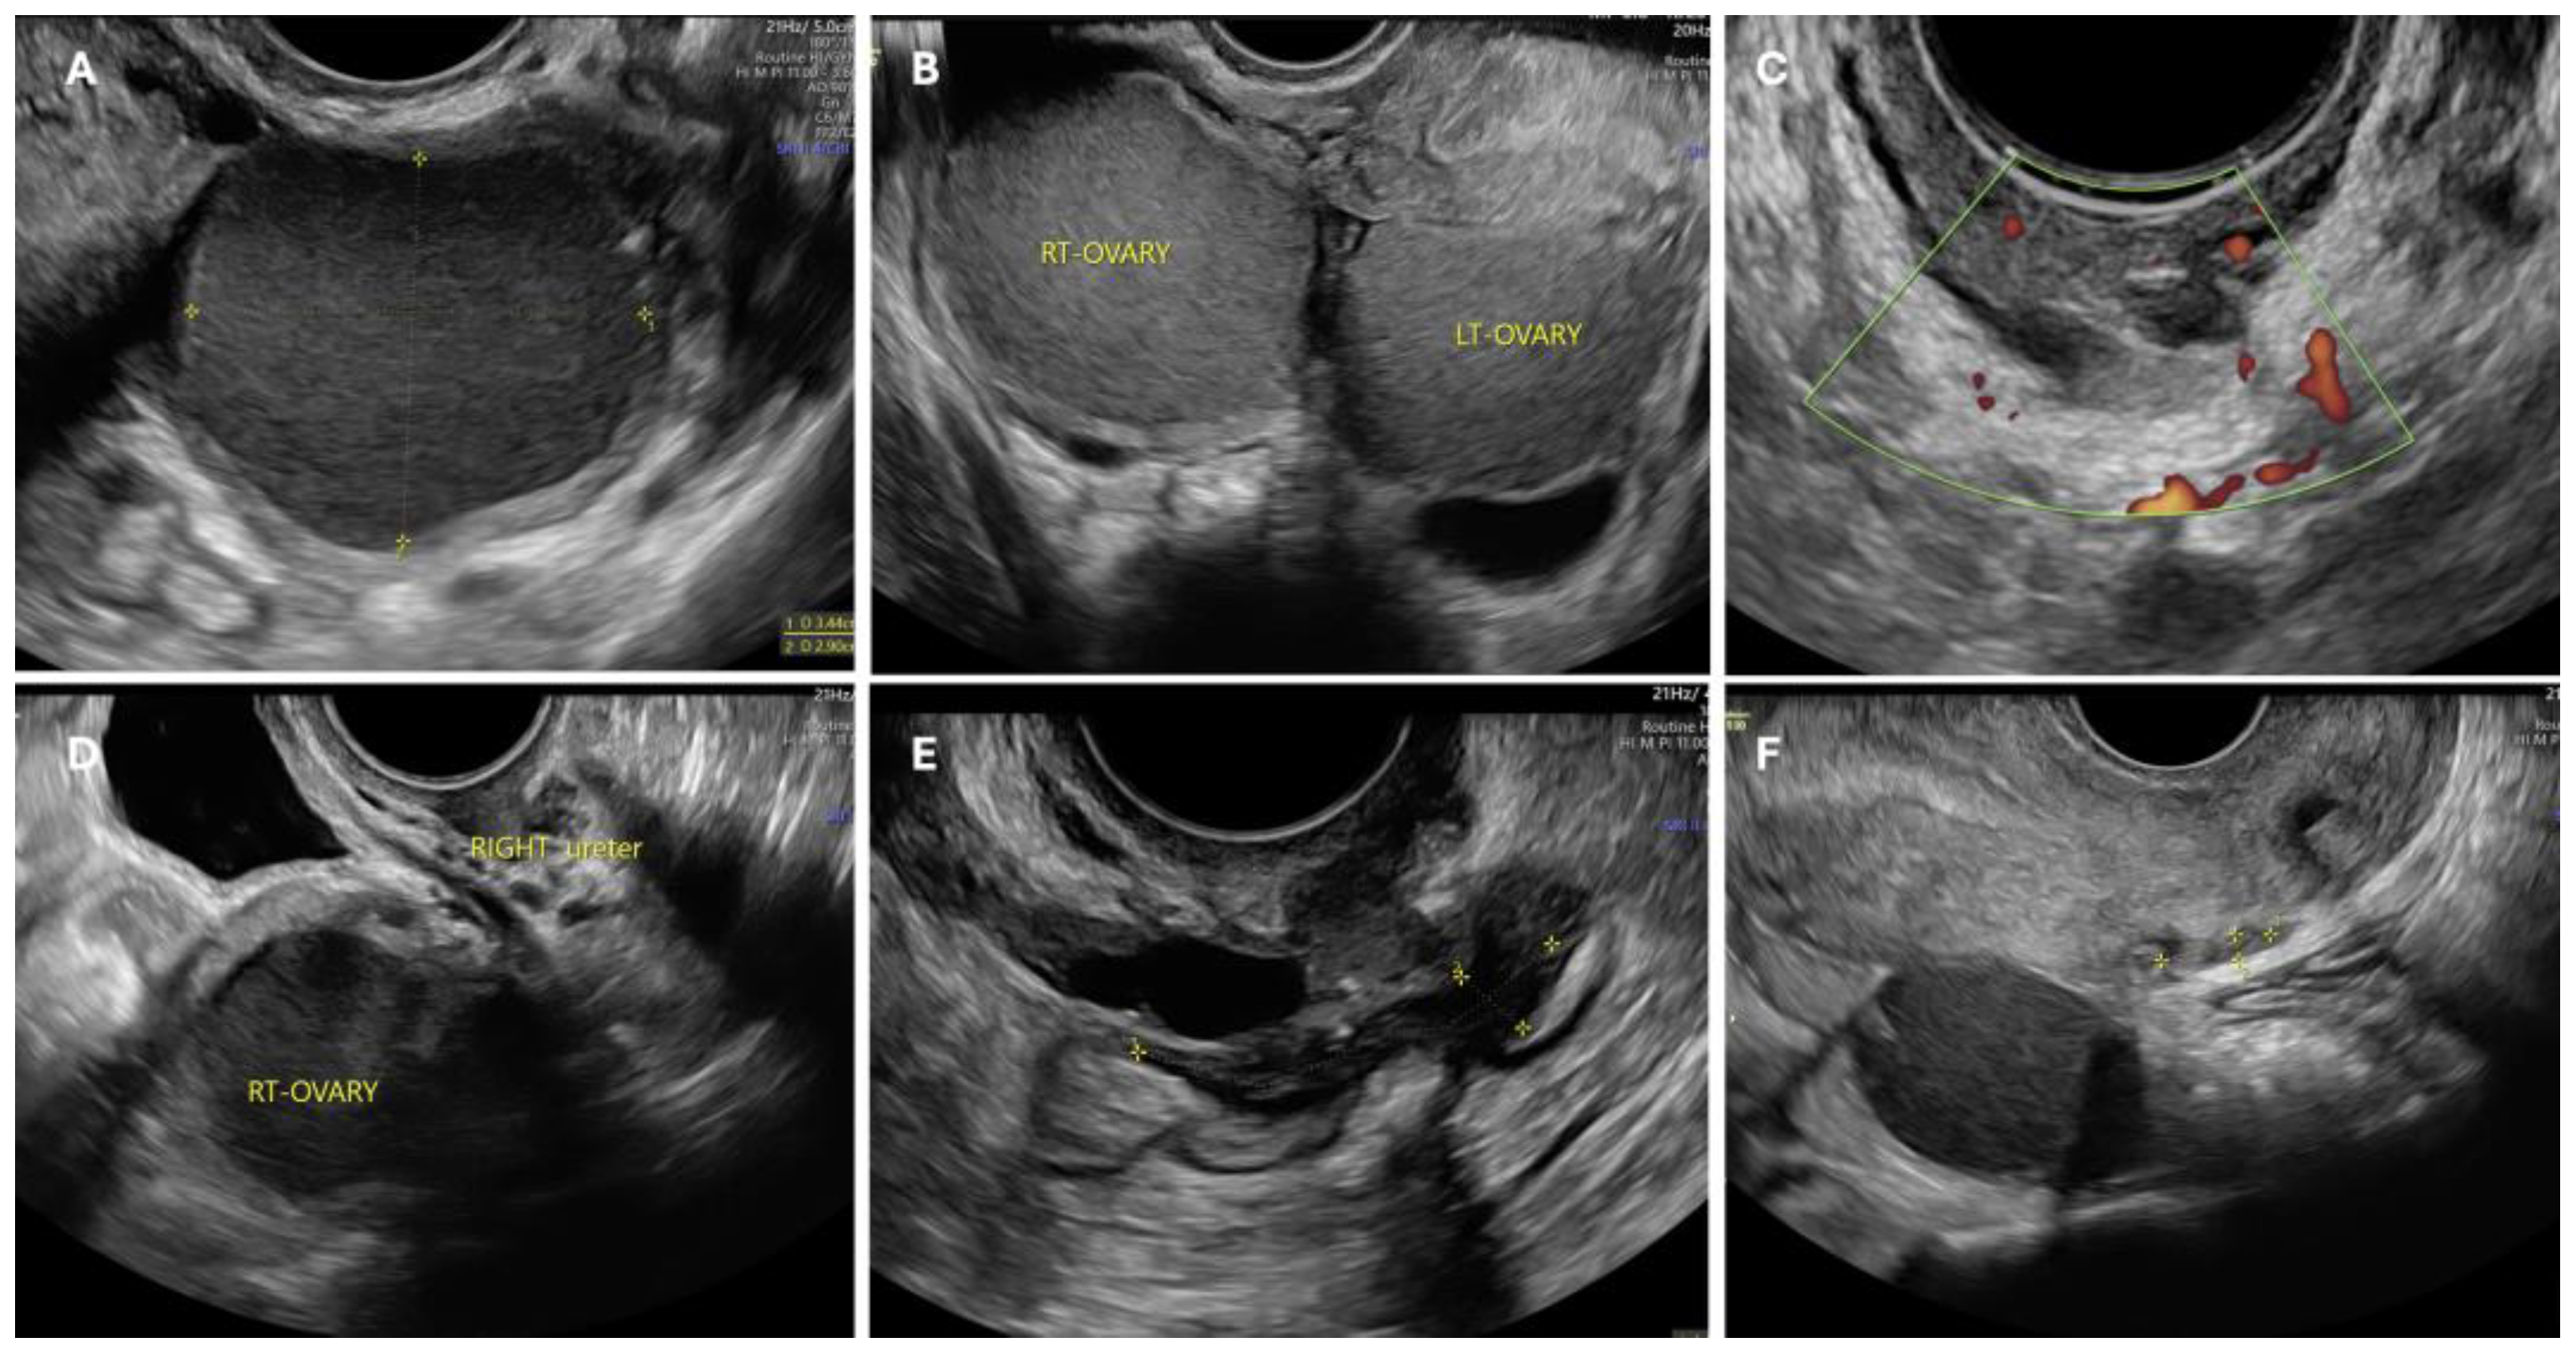

Endometriosis is often associated with infertility, furthermore, patients can experience unbearable pain requiring therapy to relieve symptoms. Unfortunately, the hormonal nature of the disease leads to undesirable contraceptive effects, making most therapies unsuitable for women wishing to conceive. Thus, the possible treatments for endometriosis-related infertility are surgery, IVF, or a combination of the two, but in the absence of specific guidelines, decisions in these cases often depend on the physician’s preference [72]. The first step in choosing a personalized treatment is to assess the presence of symptoms and the location and extent of lesions along with the patient’s requirements. Some ultrasound images of infertile patients with different locations of endometriosis lesions are shown in Figure 2. From a pro-surgery view, it seems that symptomatic women with mild disease and unexplained infertility may benefit from surgical treatment, with better reproductive outcomes compared to untreated women [73]. In addition, surgery should also be considered as a first-line option in the case of voluminous OMAs with doubtful ultrasonographic appearance [74]. It may also increase the chances of subsequent IVF by improving follicular access [50] and preventing cyst rupture during pregnancy [72] but in the case of small OMAs, literature reviews have shown that surgical treatment prior to IVF does not increase the chances of pregnancy [75]. The location of the lesions must be considered before planning surgery (Figure 3). In ovarian endometriosis, the presence of the cyst itself determines the reduction in ovarian function, but as explained above, surgical treatment can contribute to damage to the follicular reserve making the choice of treatment a challenge in which risks and benefits must be balanced. As reported above, ovarian reserve can be assessed using a variety of measures, the most commonly employed being anti-Müllerian hormone (AMH) and ultrasound antral follicle count (AFC) [76]. AHM is produced by the granulosas cell and regulates the number of primordial follicles maturing, it is an objective measure but not yet standardized and it is still unknown its value in the case of monolateral ovarian surgery. AFC is the measurement of the number of follicles with a diameter of 2–10 mm, easy to perform by transvaginal ultrasound that clearly shows the follicular activity both in the operated and non-operated ovary, but on the other hand, it shows intra- and inter-cycle variation and it is operator dependent [76]. When using AMH as a marker of ovarian function in endometriosis, we have to consider that OMAs per se reduce its value and AFC may be reduced in the affected ovary due to poor visualization of the follicles because of the presence of the cyst or an intrinsic reduction in the follicles as a result of the pathology [76]. For all these reasons, the role of preoperative and postoperative AMH and AFC is still unclear. Traditionally, cystectomy has been the preferred technique because of a reduced risk of recurrence, but it is associated with a higher risk of reduced ovarian volume and thus ovarian function [76]. Being a skilled surgeon is not always enough to treat endometriosis-related infertility, better results are only provided in the case of extensive experience of a “dedicated endometriosis” surgeon who is able to assess how radical to treat the disease, restore the pelvic anatomy and avoid ovarian or tubal injury [77].

Figure 2.

Different ultrasonographic cases of pelvic endometriosis. Ovarian involvement may be unilateral (A) or bilateral (B), giving the characteristic ‘kissing ovaries’ sign when the two affected ovaries are attached posteriorly to the uterus. Parametrial endometriosis, nodule involving the right ureter (C). It is important to note that pelvic structures are closely located and therefore it is common for adjacent structures to be infiltrated or retracted by endometriosis, as in the case of the ureter (D,F). Figure (E) shows a case of endometriosis of the anterior wall of the rectum. Often the lesions are multiple, resulting in complex presentations with possible involvement of the ovary, uterosacral ligaments, and rectum, resulting hypomobility of the structures, Douglas’ obliteration and even frozen pelvis.